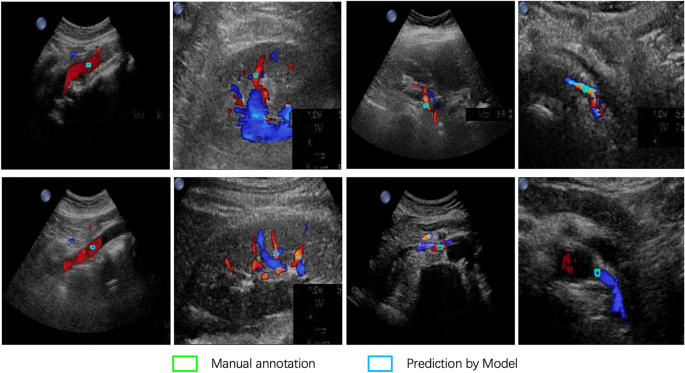

In Fig. 6, examples of predicted sampling positions by the optimal object detection model on the clinical validation dataset are illustrated. Only the sampling position with the highest probability is plotted with a blue rectangular box. It is evident that the predicted results closely align with the manually labeled sampling positions, illustrating that the Double Head R-CNN model effectively learned the pattern of sampling position selection.

Examples of predicted sampling positions by the Double Head R-CNN model for different types of CDS images.